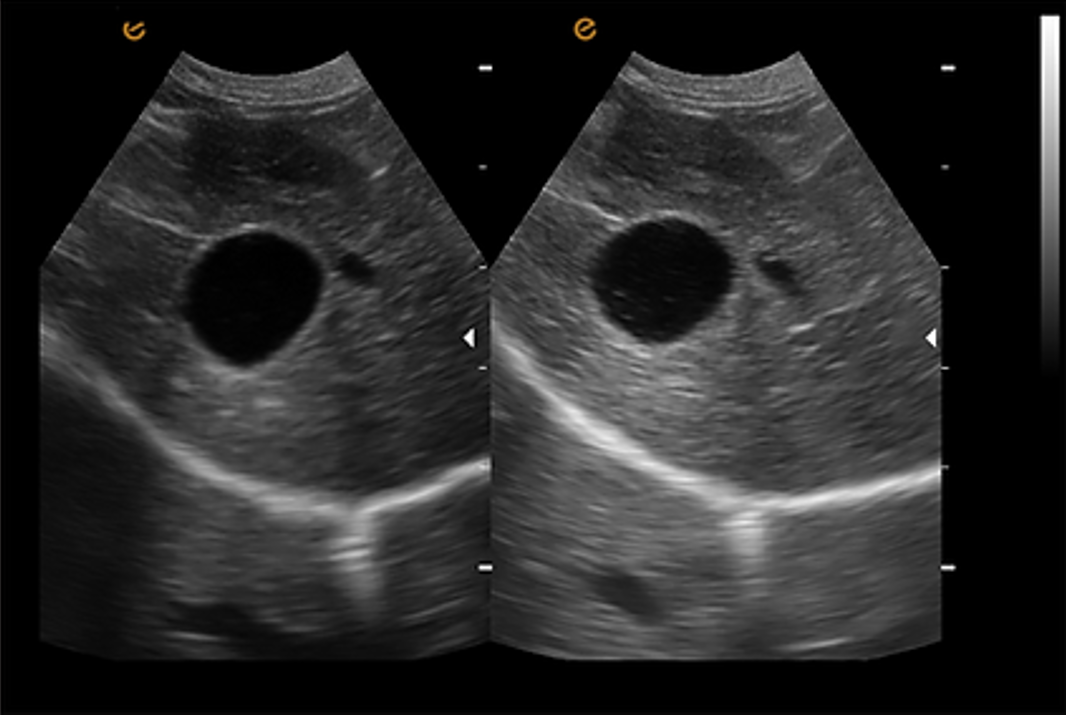

การถ่ายภาพขยาย ชุดหัวตรวจแบบอาร์เรย์นูน (Convex Array Probe) รองรับการถ่ายภาพขยาย ซึ่งช่วยขยายขอบเขตการสแกนของหัวตรวจอย่างมีประสิทธิภาพ ตอบโจทย์การใช้งานในด้านสูติศาสตร์, นรีเวชวิทยา และการวินิจฉัยที่ต้องการพื้นที่กว้าง รวมถึงการสังเกตสภาพของเนื้อเยื่อที่มีการบาดเจ็บและเนื้อเยื่อสำคัญ |